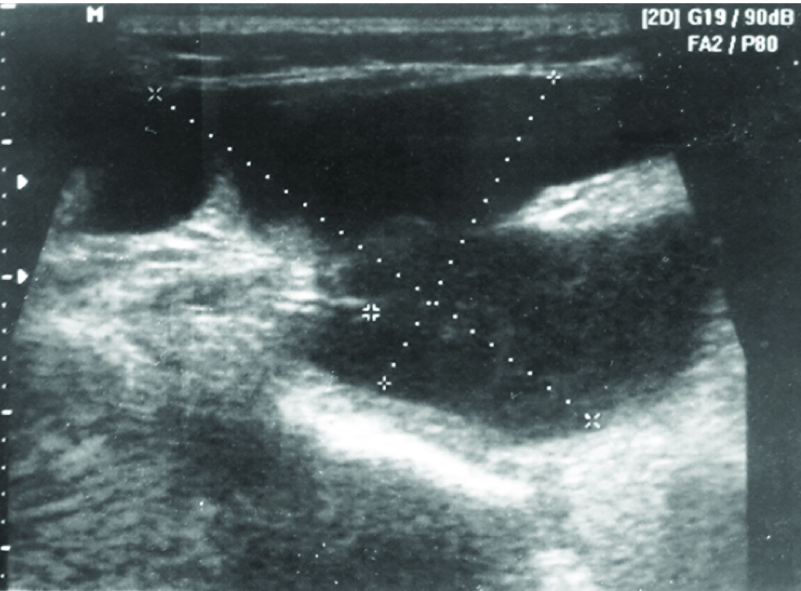

Ultrasonography was advised to study nature, size and extent of the lesion. The ultrasonogram (using 5-9 MHz linear probe) showed a hypoecogenic oval mass of 75x32 mm size, with thin wall and incomplete septae in the left submandibular region, suggestive of a benign cystic lesion [[Table/Fig-2]. Magnetic Resonance Imaging (MRI) showed well defined lobulated, round to oval lesion with smooth margins, measuring approximately 6x2.9x2.8 cm [Table/Fig-3a,b]. The lesion was present predominantly in the submandibular region on left side. Superiorly the lesion was extending upto the sublingual space on the left side superior to the mylohyoid muscle. Inferiorily it extended below the mylohyoid muscle, upto the level of superior margion of thyroid gland. Laterally, the lesion migrated till the platysma. However, no obvious extension through the platysma was seen. Medially the lesion was seen compressing the submandibular gland in its superior aspect and reaching upto the midline in its inferior aspect. MRI findings were suggestive of a well defined cystic lesion predominantly in submandibular space, having extensions into sublingual space [Table/Fig-3a,b].

Ultrasonogram showing a large hypoecogenic cystic lesion in left submandibular region